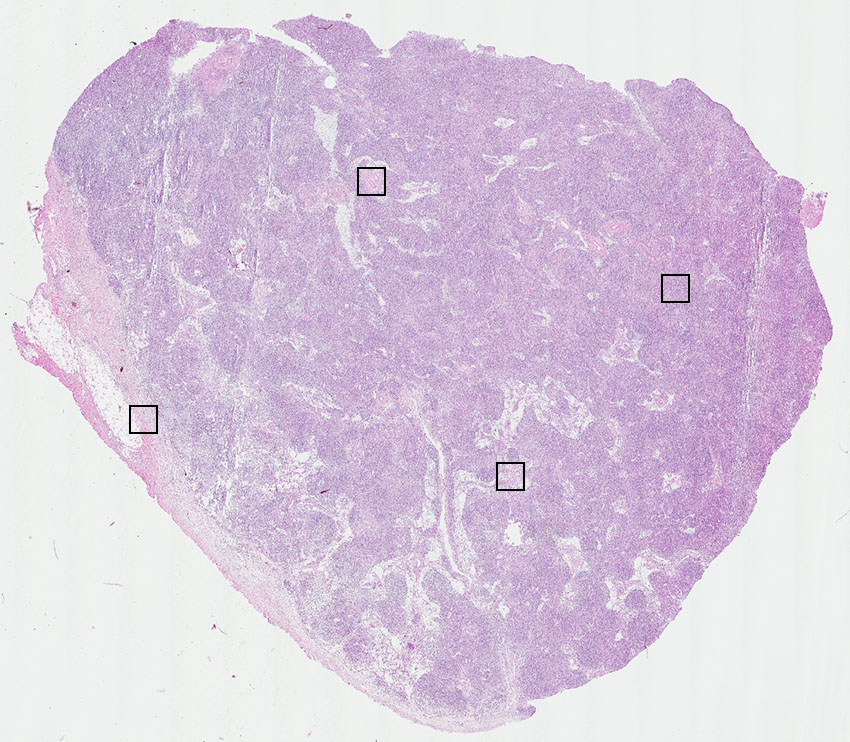

Lymphocytes:

85

Other cell types:

15